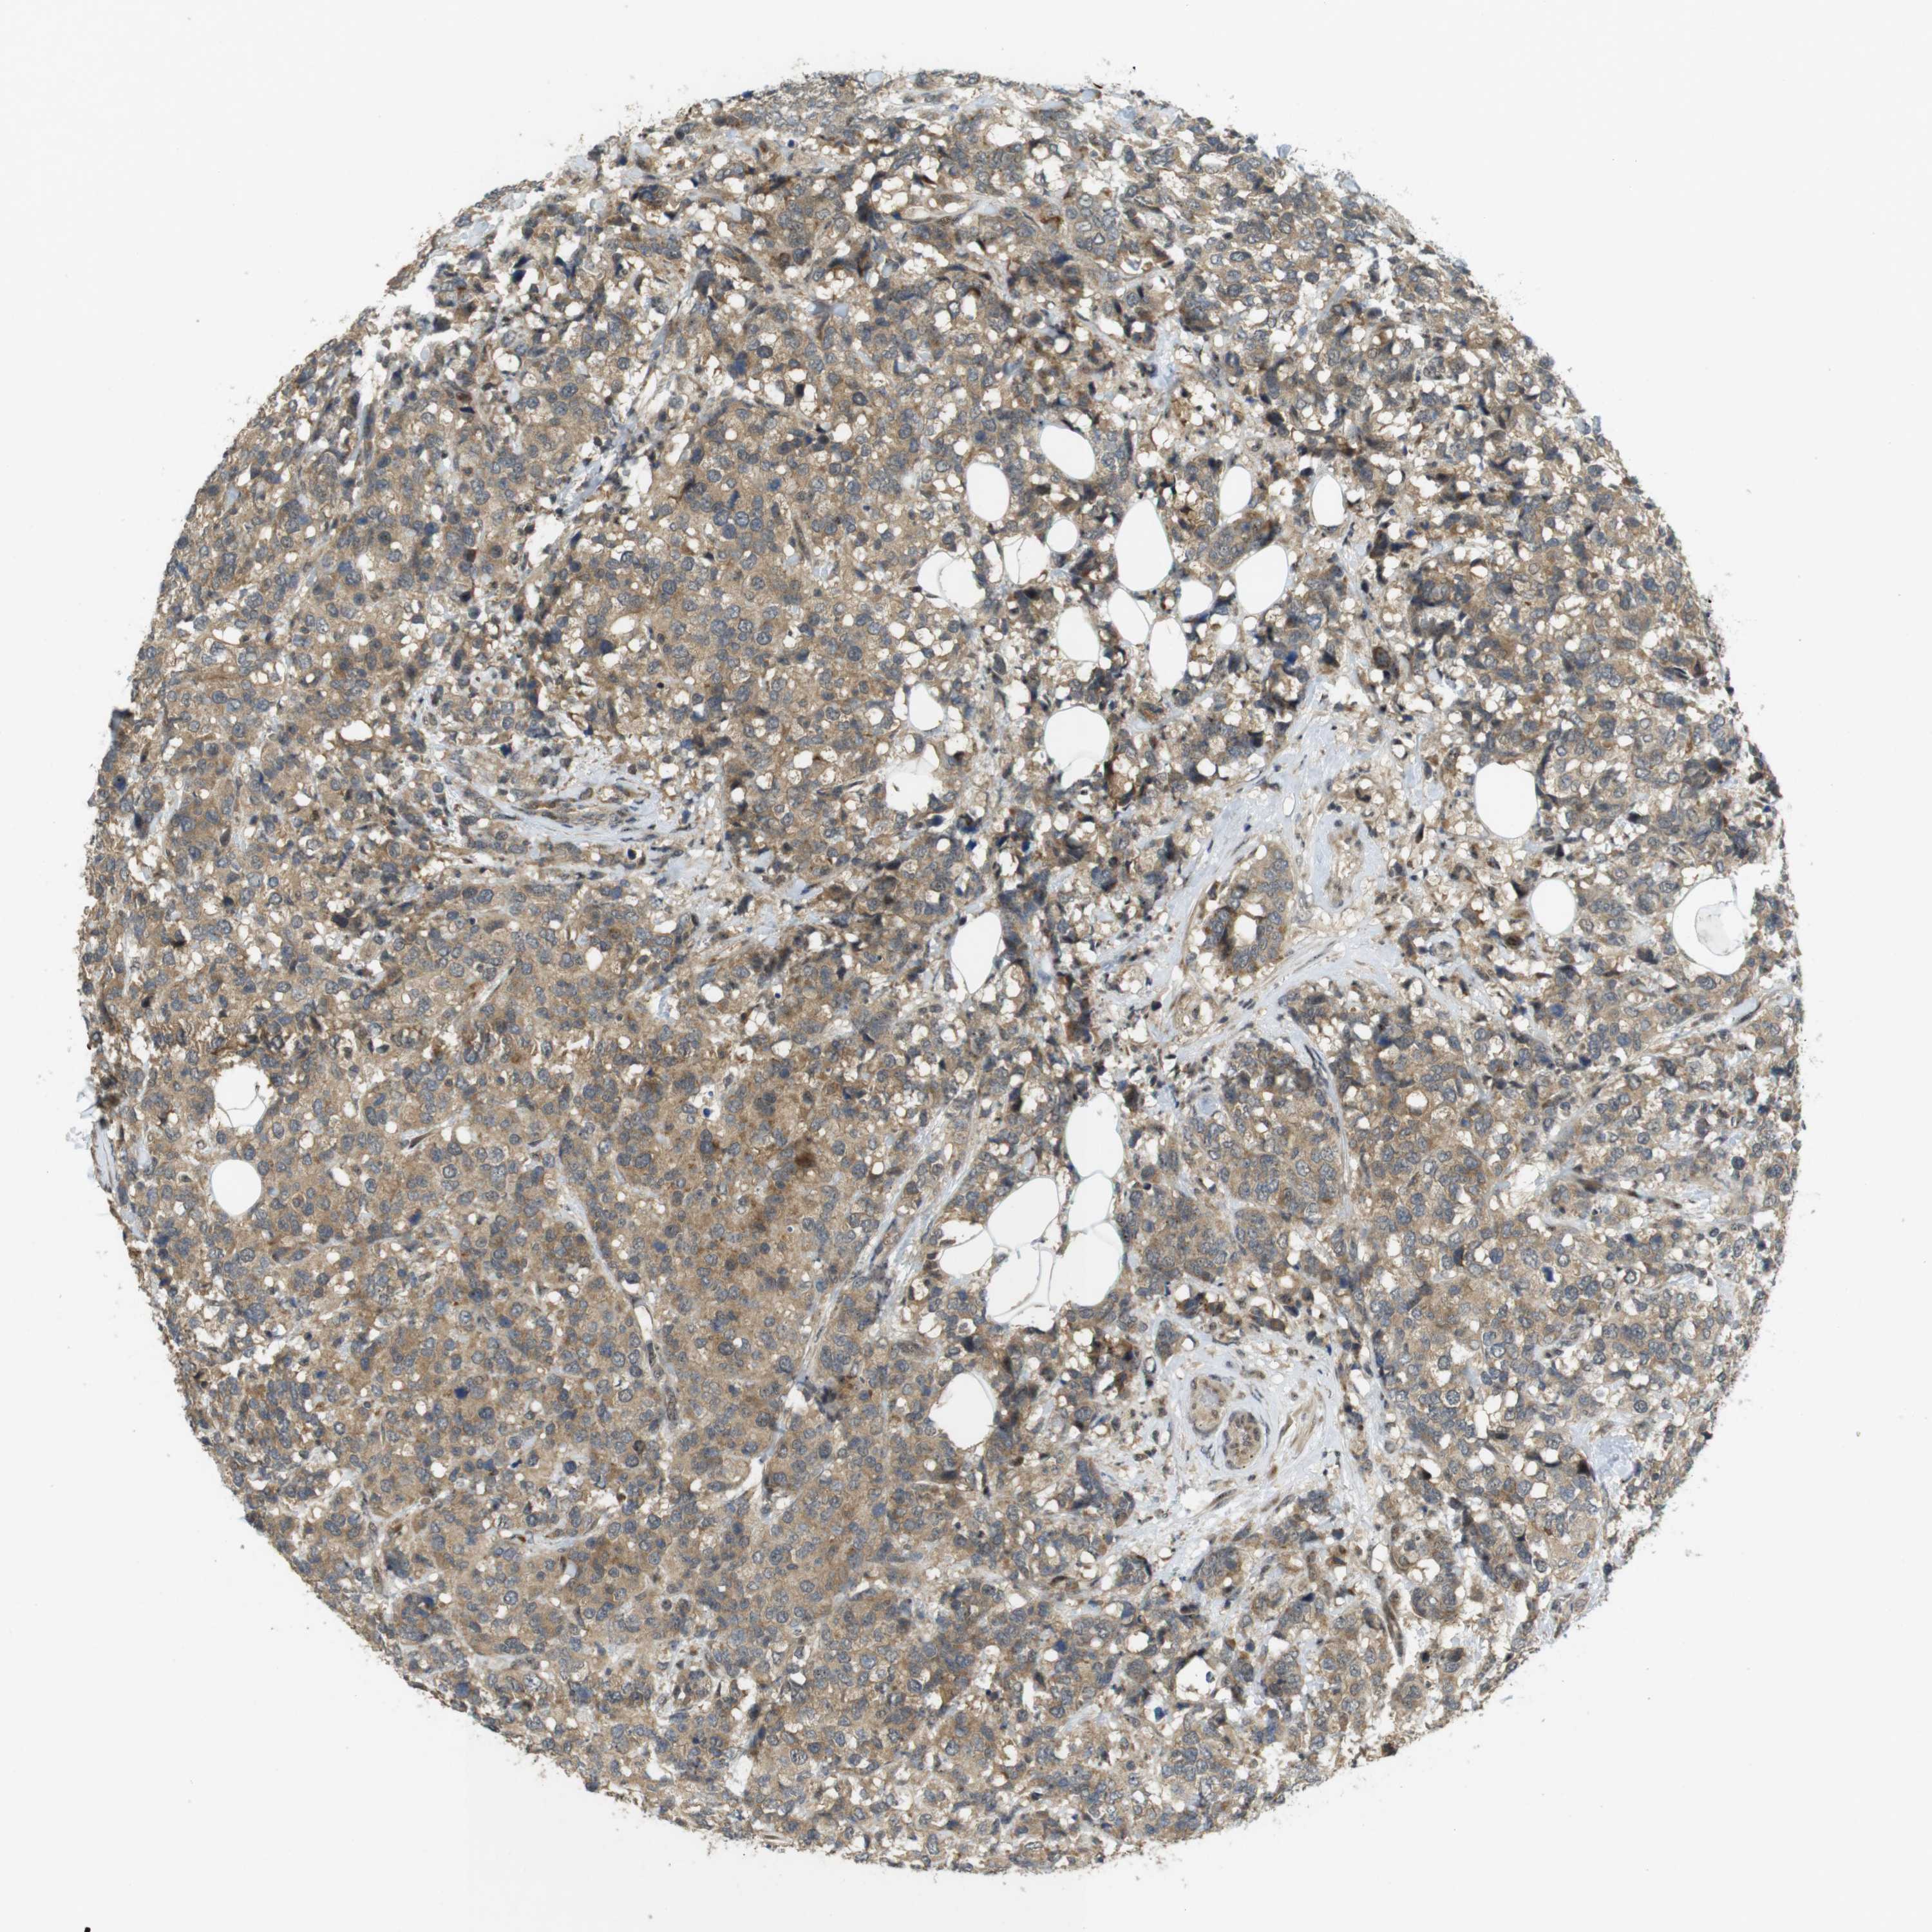

CANCER BREAST CANCER Show tissue menu

BRCA TCGA BRCA VALIDATION PROTEIN EXPRESSION